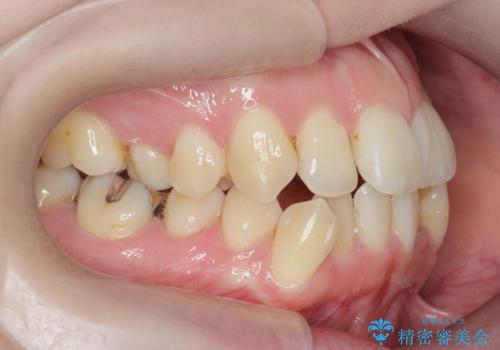

前歯のがたつき すれ違い咬合のマウスピース矯正治療

- 前歯のがたつきや歯の角度、矯正治療を希望され来院されました。

下顎が前にある咬合関係を可及的に咬合移動で改善し、IPR、下顎3前歯の仕上げで行うマウスピース矯正を計画します。